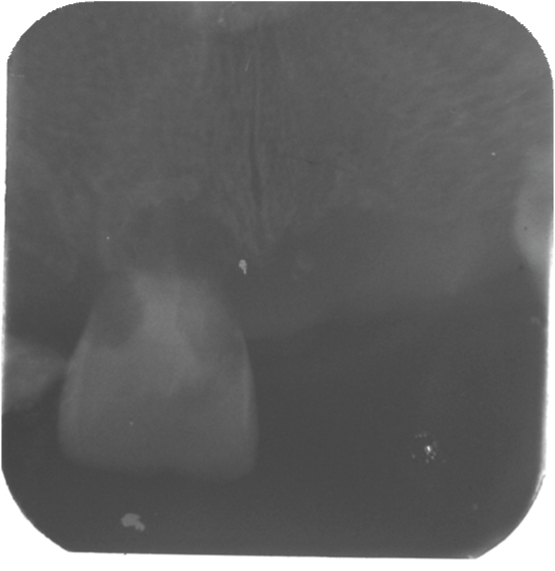

[Table/Fig-3] showing the normal morphology of crowns of the maxillary teeth. [Table/Fig-4] showing the normal morphology of crowns of the mandibular teeth. Full mouth intraoral periapical radiograph revealed complete root resorption in relation to 11, 12, 41 and 42; cervical resorption in 15, 33, 34 and 43, 44; apical resorption in 16, 24, 25 and 26. Resorption in both apical and cervical region was noticed in relation to 35, 36 and 46. Panoramic radiographs showed multiple ill defined radiolucent areas in apical third and cervical region of all teeth in varying degree. Lateral view of skull showed no evidence of any skull changes. In [Table/Fig-5] intraoral periapical radiograph showing complete root resorption in relation to 11 and 12. In [Table/Fig-6] intraoral periapical radiograph showing complete root resorption in relation to 41 and 42. In [Table/Fig-7] intraoral periapical radiograph showing cervical resorbtion in relation to 15 and apical root resorption of mesial and distal roots in relation to 16. Loss of PDL space in 17 can be appreciated.

Intraoral periapical radiograph showing complete root resorption in relation to 11 and 12